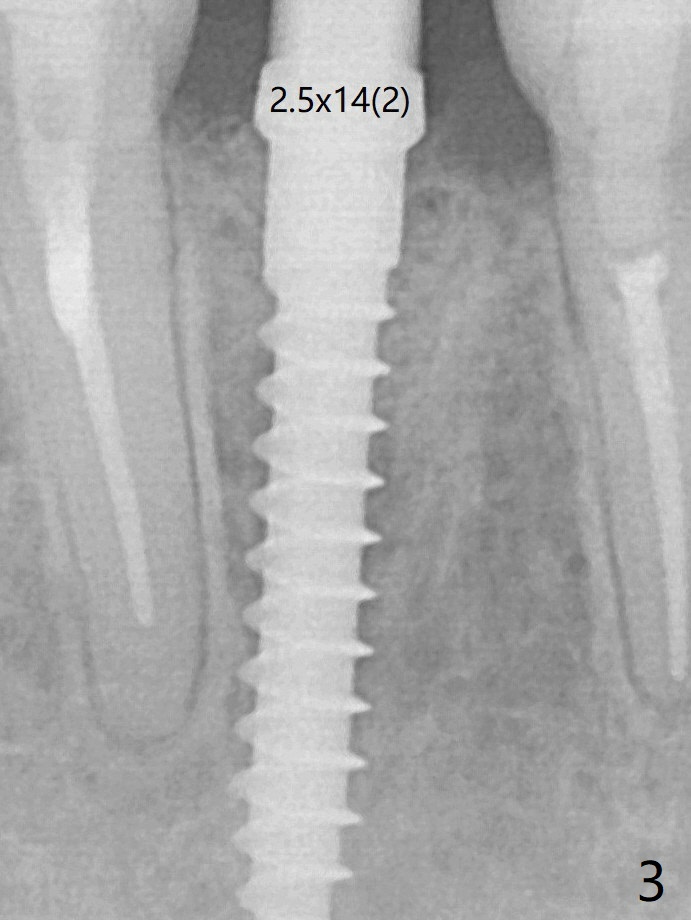

A drawback of implant planning at #25 is not to use a preop PA (Fig.1 (^ fracture line)). The initial trajectory seems to be alright (Fig.2 (red line: socket; D: 1.2 mm drill)), but a 2.5x14(2) mm implant placed is close to the tooth #26 (Fig.3 (allograft having been placed)). The latter may be related to more bone loss in the distal crest 3.5 months postop (Fig.8) and more severe distal papillary recession (Fig.9 *). The meisal bone seems to be wider.